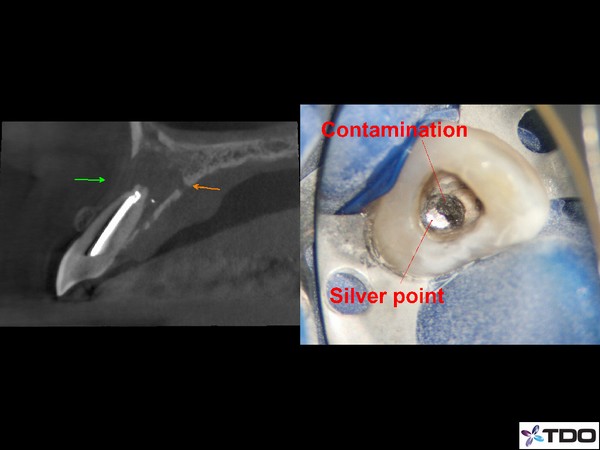

This patient fractured her front tooth.  The crown was only 2 years old.  Extraction and implant placement was recommended.  It would have been a challenging case esthetically.  We were able to retreat the contaminated root canal.  Posts were placed for reinforcement.  We were able to use the existing crown by retrofitting it.  We managed the occlusion to mitigate the risk of future fracture.